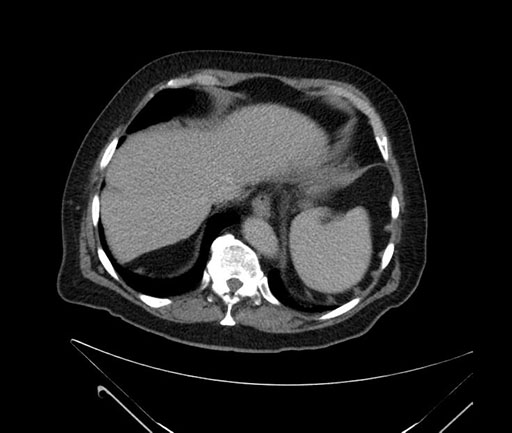

Whipple (pancreaticoduodenectomy) [case 7]

Imaging Analysis

Look through the patient's CT scan to identify any areas of concern for the necessary procedure.

Axial - stented